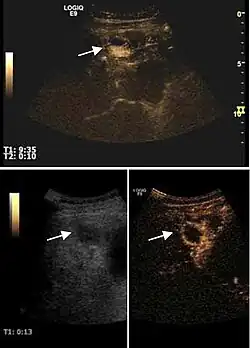

The ultrasound appearance is a well defined lesion, with very thin, almost unapparent walls, without circulatory signal at Doppler or CEUS investigation. The content is transonic suggesting fluid composition. The presence of membranes, abundant sediment or cysts inside is suggestive for parasitic, hydatid nature. Posterior from the lesion the acoustic enhancement phenomenon is seen, which strengthens the suspicion of fluid mass. They typically displace normal liver vessels but no vascular or biliary invasion occurs.

Liver cyst

Hydatid liver cyst. Diagnostic criteria are the presence of membranes and sediment inside.